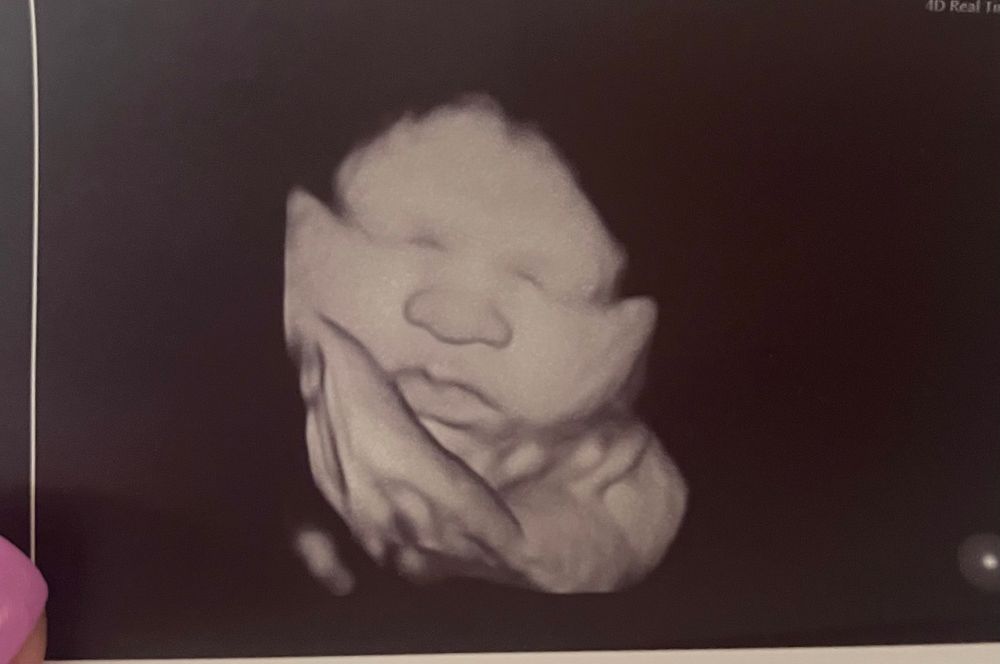

3d узи на поздних сроках)

я тут была на узи в 36 недель и врач-узист сказала цитирую «СД видно на узи на последних неделях, что вы переживаете» «ваша не похожа»

я прям вглядываюсь в свои фотокарточки) а как думаете вы?)

Какой милейший ребёнок! Прелесть!

На хорошем аппарате и правда видны некоторые признаки: разрез и посадка глаз, нос шире рта. У вас ничего этого нет)